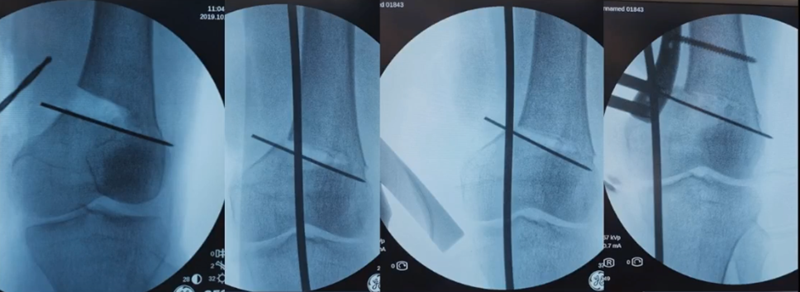

合页点和截骨线已确定好,按照术前计划打入导针,测量截骨深度。

注意,目前临床推荐的DFO要求最好能做双平面截骨,即还要有一条上行截骨线,上行截骨线与水平截骨线夹角大概为95° 左右。这种截骨方式一方面可以增加稳定性,同时也可以减少对上方髌股关节的干扰。

上行截骨时,要保持肢体旋转中立位,前方要有骨撬保护,由内向外完全截开,上行截骨线不存在合页。

水平截骨时,同样放肢体中立位,后侧放一把骨撬保护后方重要结构。

截骨过程中,不要求一次截骨到位,把合页深度全部截到,可以留最后一点,用钻头由前向后打出一排筛孔来,把合页端弱化,再去做闭合时就不容易折断了。

(1)合页骨折

对于术中出现的合页骨折,此时还有一定的稳定性,可以调整力线固定以后,由前外向后内打一根防旋螺钉,这样仍然是比较稳定,术后康复计划与正常一样。

对于术中合页骨折,但非常不稳定、无法控制力线的情况,可以由外侧向股骨外髁打入一枚2.0的克氏针,因为克氏针具有一定弹性,相当于重建合页临时稳定性,在此基础上再去调整力线,做固定。